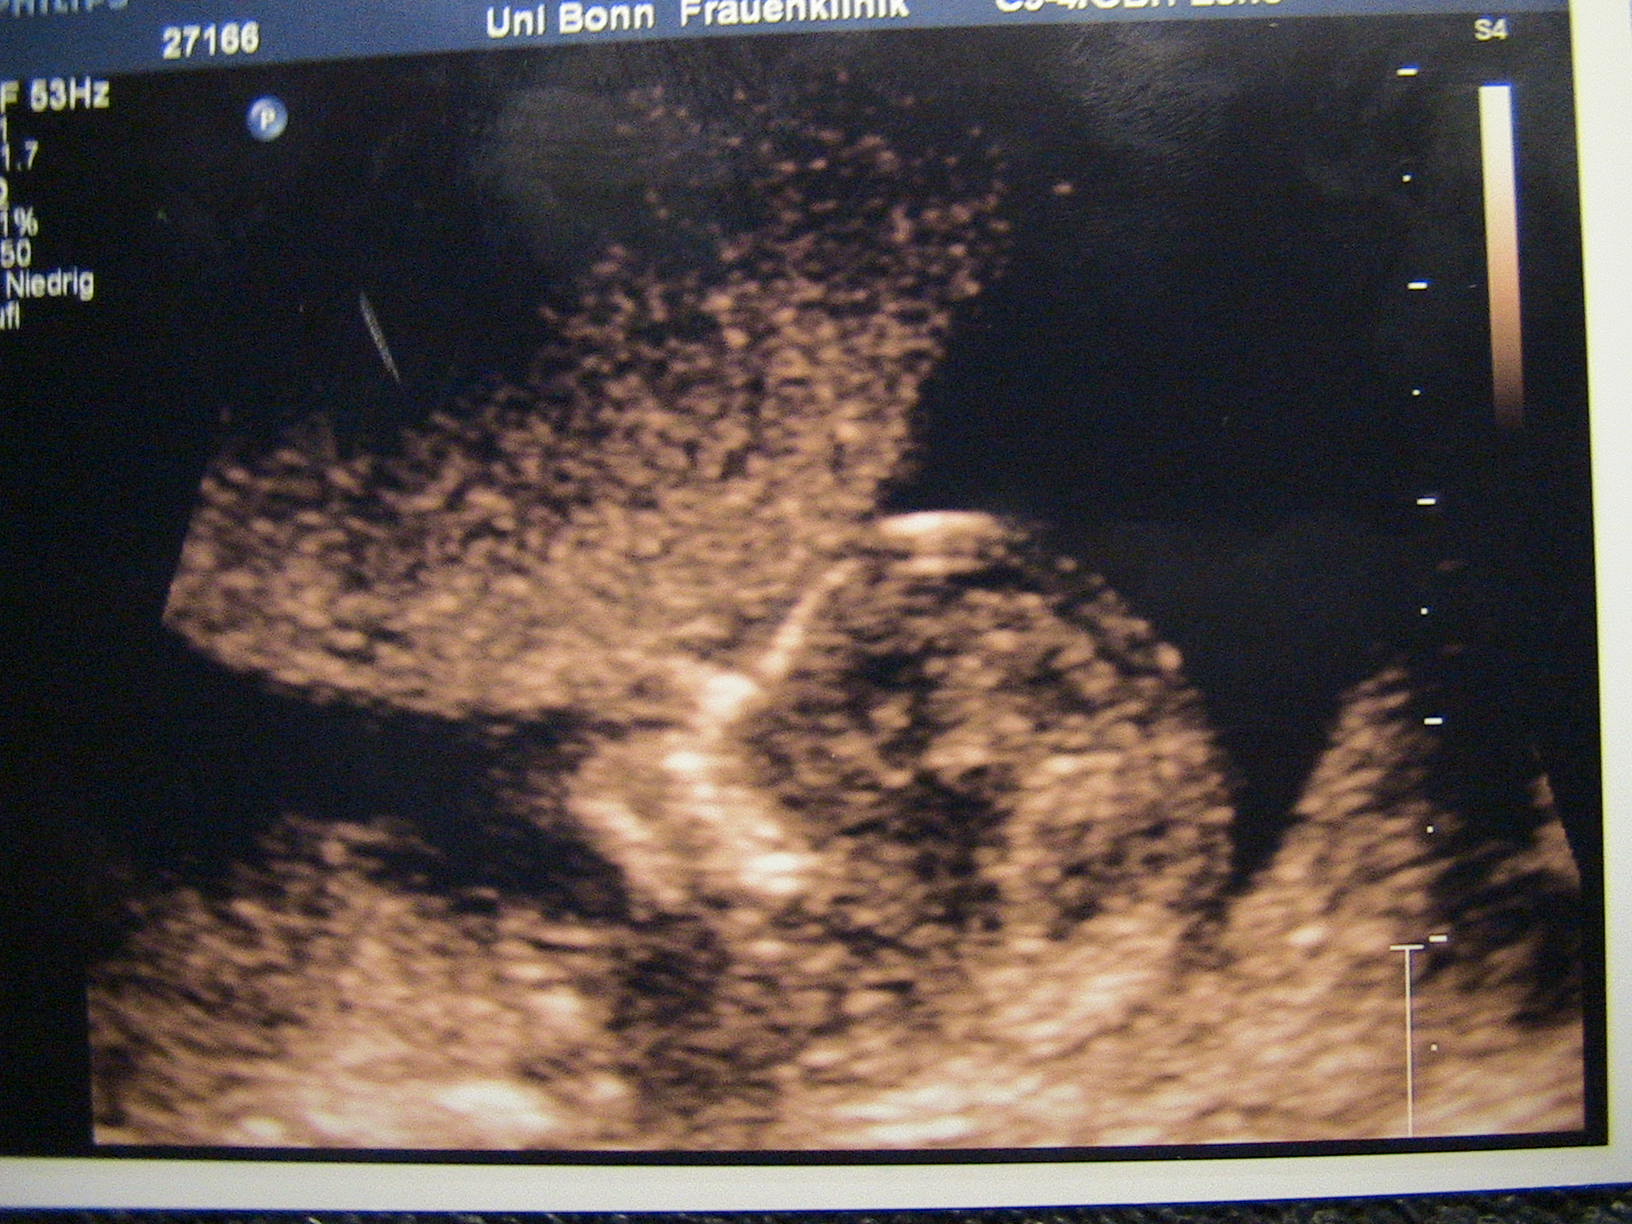

Ihr wartet sicher schon ganz gespannt auf mich.also wir sind erst mal heute Morgen zur Hämatologien gefahren,habe dann 8Röhrchen Blutdagelassen da ja alle 4Wochen die Blutgerinung kontolliert wird.So da waren wir von 9Uhr bis 9uhr45 ging ja recht schnell dann ab zur Nf Messung an die Uni oh man ich war mega aufgeregt wir dort um halb 11 angekommen das ganze warte Zimmer voll ich immer Nervöser.Plötzlich gegen 12uhr 30 wurden wir endlich aufgerufen .Erst fragte sie uns einige sachen und dann meinte sie legen sie sich dann mal hin ich wollte mich gerade ausziehen da meine die Ärztin ne wir machen es vom Bauch.Ich sagte da sieht man bestimmt noch nichts bin erst 12plus 3 ach wir schauen mal.Gesagt getan mein Schatz durfte sich an einen Grossen Bildschirm setzten.Dies und das wurde gemessen und es sieht alles super aus.Auch darf ich weiter zur Kontrolle durch die Freu . Dann kam noch der Chef Arzt der mich auch noch mal untersuchte da saß es im schneidersitz und winkte mit dem Füsschen alles in bester Ordnung dann aufeinmal fragte er möchten sie das Geschlecht wissen wir jaaaaaaaaaaaaaaaaaaaaaaaaaaaaaaaaaaaaaaaaaaaaaaaaaaaaaaaaaaaaaaaaaaaaaaaaaaaaaaaaaaaaaaaaaaaaaaaaaaaaaa.Tja jetzt bin ich am Überlegen ob ich es euch verraten sol Ich bzw.wir sind mega Glücklich es wird ein................................

JUNGE mein Mann freut sich wie ein schneekönig danke für euere Daumen

unser Junge!

Dateianhänge

007.JPG